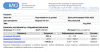

ШикТест энантат PL 125мг 1 раз в 4 дня.

Анализ после 4ой инъекции через 24 часа.